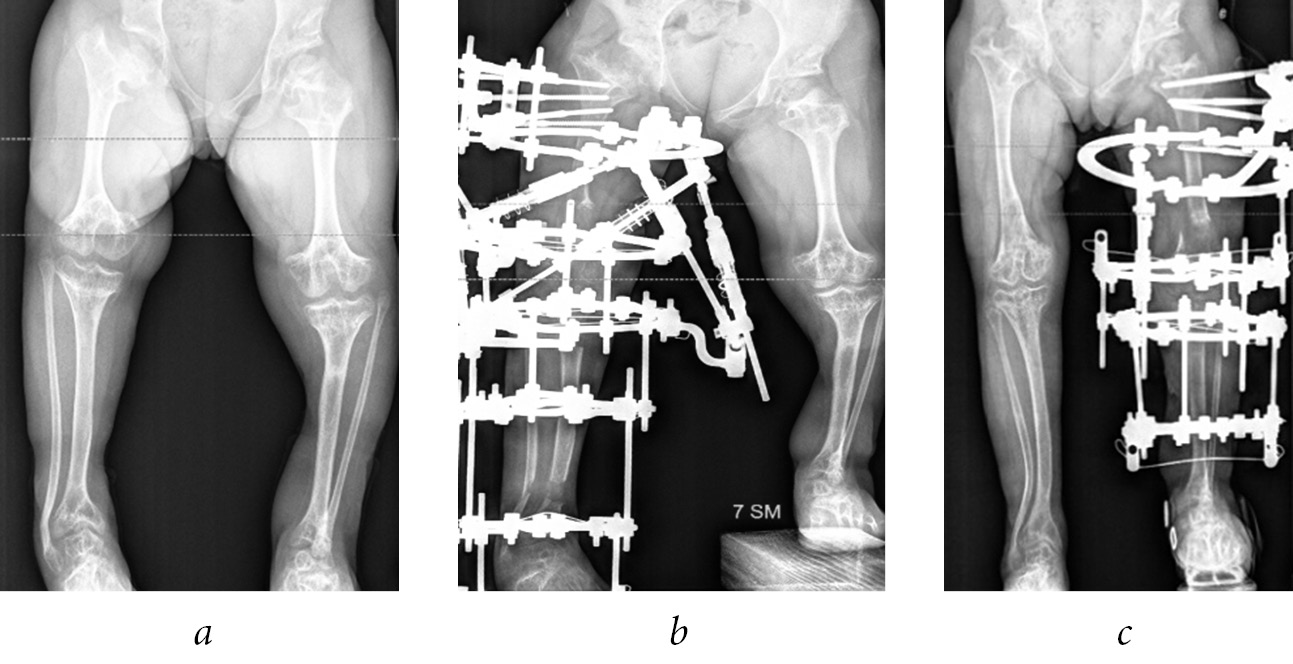

The shortening of the lower limb by 4 cm or more, the shoulder by 6 cm or more, and the forearm by 5 cm or more were considered an indication for surgical treatment, taking into account the age of the child. In the presence of angular deformities of the limb segments, accompanied by a shortening of 3 cm or more, one-stage correction of the length and shape of the limb segment by osteotomy was performed using compression-distraction osteosynthesis. At the final stage of treatment, to correct the multiplanar deformities of the bone metaphyses forming the knee and ankle joints, the Ortho-SUV reposition unit was used in three patients, which allowed to reduce the time and improve the quality of reposition (Fig. 1).

Fig. 1. Radiographs of patient G.’s lower extremities before (a) and during the correction of the shape and length of the right and left lower extremities using the Ortho-SUV reposition unit (b) and the standard layout of the Ilizarov apparatus (c)